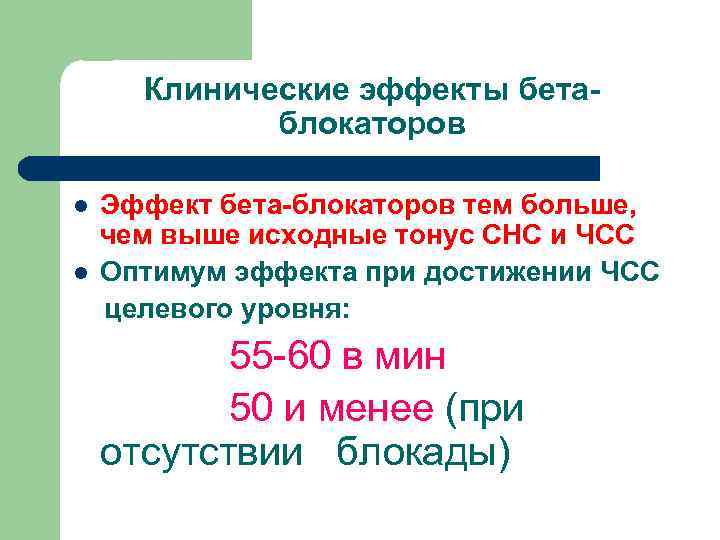

Клинические эффекты бетаблокаторов l l Эффект бета-блокаторов тем больше, чем выше исходные тонус СНС и ЧСС Оптимум эффекта при достижении ЧСС целевого уровня: 55 -60 в мин 50 и менее (при отсутствии блокады)